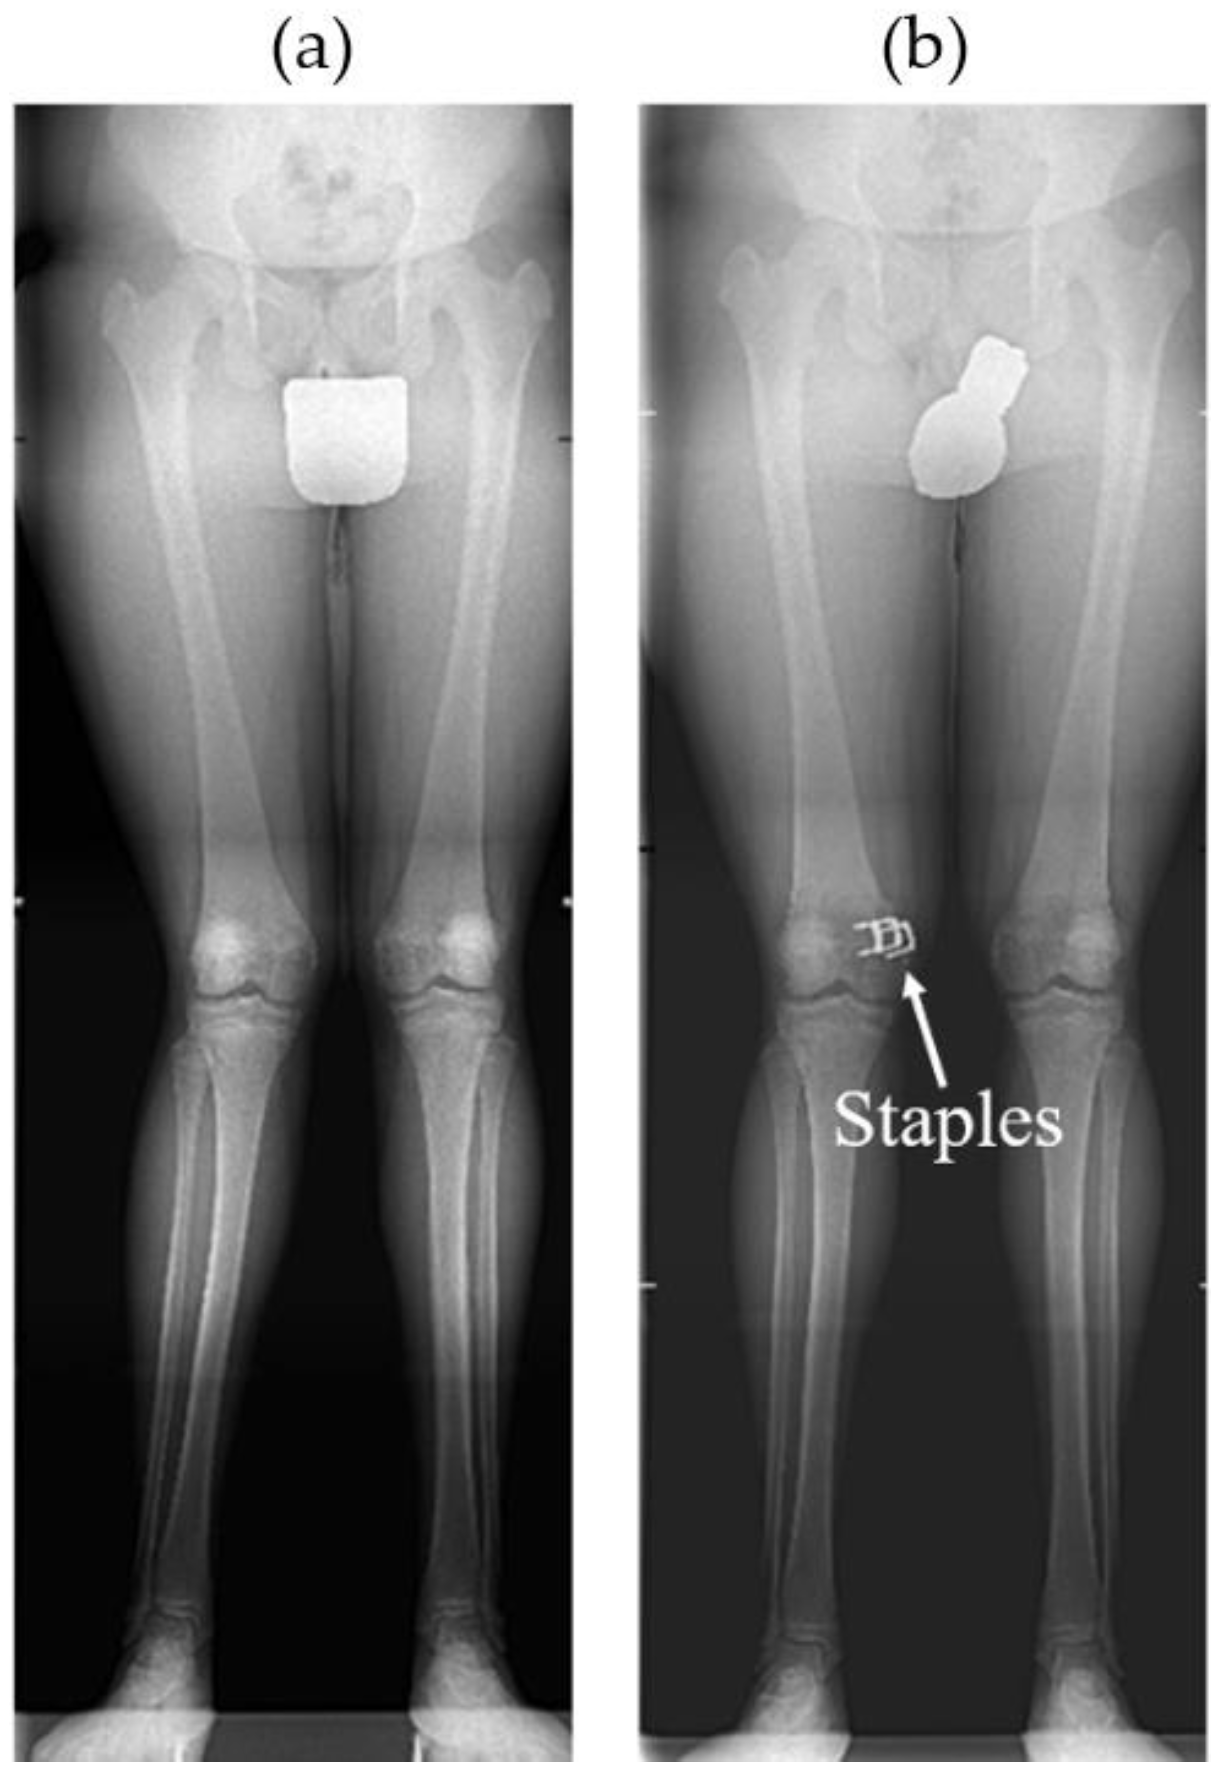

Using staples, the physis (epiphyseal plate) can be relatively simply restrained either on both sides when correcting limb length discrepancy (i.e., “epiphysiodesis”) or only on one side when correcting angular deformities (i.e., “hemiepiphyseodesis”) (see Figure 1 and Figure 2). Unlike the irreversible method of permanent epiphysiodesis, see [8], epiphyseal stapling does not destroy the epiphyseal plate and, therefore, allows resumption of the growth once the optimal correction is achieved; see [4].

According to [1,4], besides accurate diagnosis confirmed by a radiogram of the whole limb (see Figure 2), good timing of the treatment is also very important. The surgical procedure involves a short longitudinal incision through soft tissues over the physis and extraperiosteal implantation of the staple using a special instrument under radiography control [11] (see Figure 3). The staple must bridge the physis but not penetrate it to prevent its impairment (see Figure 4).

Figure 2. (a) Long radiogram of preoperative genu valgum and (b) consecutive correction with staples in femur; see [4].